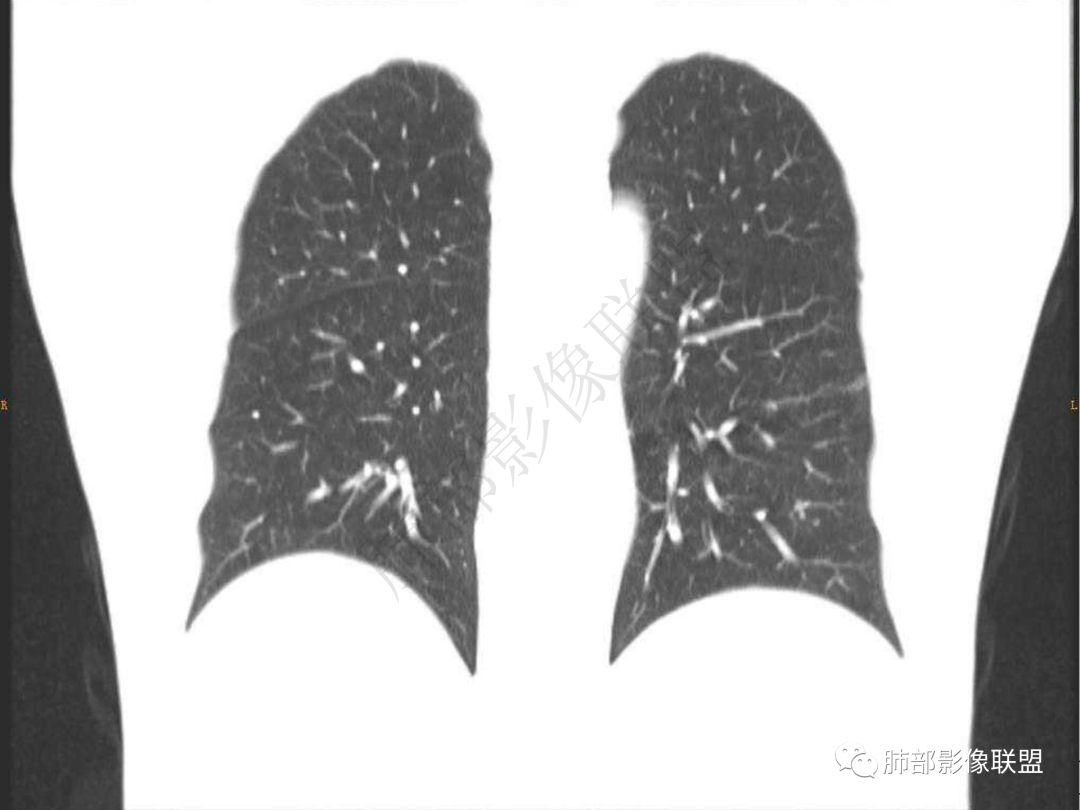

1.中年男性,咳嗽咳痰20余天,间断咯血2周

2.左肺下叶团片影,跨背段及内前基底段,实性部分类椭圆形,密度不甚均匀,可见毛刺及棘状突起,未见典型分叶及胸膜凹陷。病灶上下缘可见相应肺段支气管旁进侧出,管壁轻度增厚,未见狭窄阻塞。

3.周边较大范围磨玻璃影,边界相当模糊,小叶增厚明显。注意叶裂另一侧、左肺舌段亦可见磨玻璃影及增厚的小叶间隔。未见明确卫星病灶。

4.实性部分不均匀环形强化并显示一小范围低密度坏死区或空洞。较之肺窗,整体纵隔窗范围较小,提示病灶并不十分密实。抑或为不同时段图像。

5.双肺门及纵隔未见增大淋巴结。未见胸腔积液。